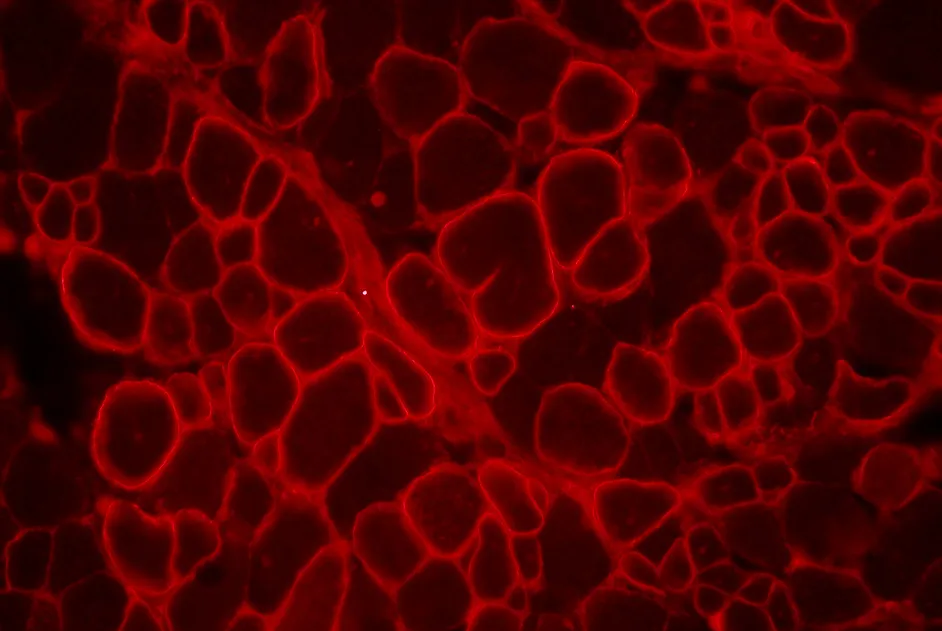

La myopathie de Duchenne (DMD) est due à des mutations dans le gène codant la dystrophine. Une piste de thérapie génique consiste à introduire un gène codant une microdystrophine à l’aide d’un vecteur viral (de type virus adéno-associé ou AAV). Cette approche a montré son efficacité dans des souris modèles de DMD. Appliquée à de très jeunes chiots modèles de DMD (âgés de 2 à 4 jours), elle a entrainé un retard de croissance et une atrophie musculaire.

Dans un article publié en août 2015, une équipe américaine rapporte la mise au point d’une thérapie génique dans 3 chiens modèles de DMD, âgés de 2 mois. Dans cette étude, le vecteur AAV, qui transporte le gène de la microdystrophine, a été modifié au niveau de son enveloppe dans le but d’entrainer une moindre réponse immunitaire lorsqu’il sera injecté dans le chien modèle.

Le produit de thérapie génique ainsi mis au point et administré par voie intraveineuse a été bien toléré par les chiens traités. Il a été retrouvé dans les muscles squelettiques ainsi que dans le diaphragme et le cœur. Les chiens n’ont pas présenté de retard de croissance.